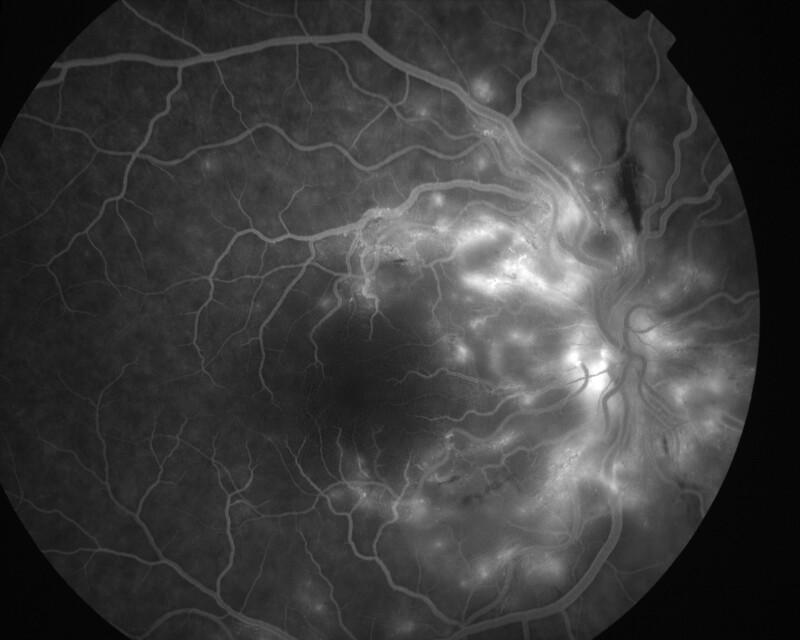

RETINOPATHIE HYPERTENSIVE

IM000020.jpg